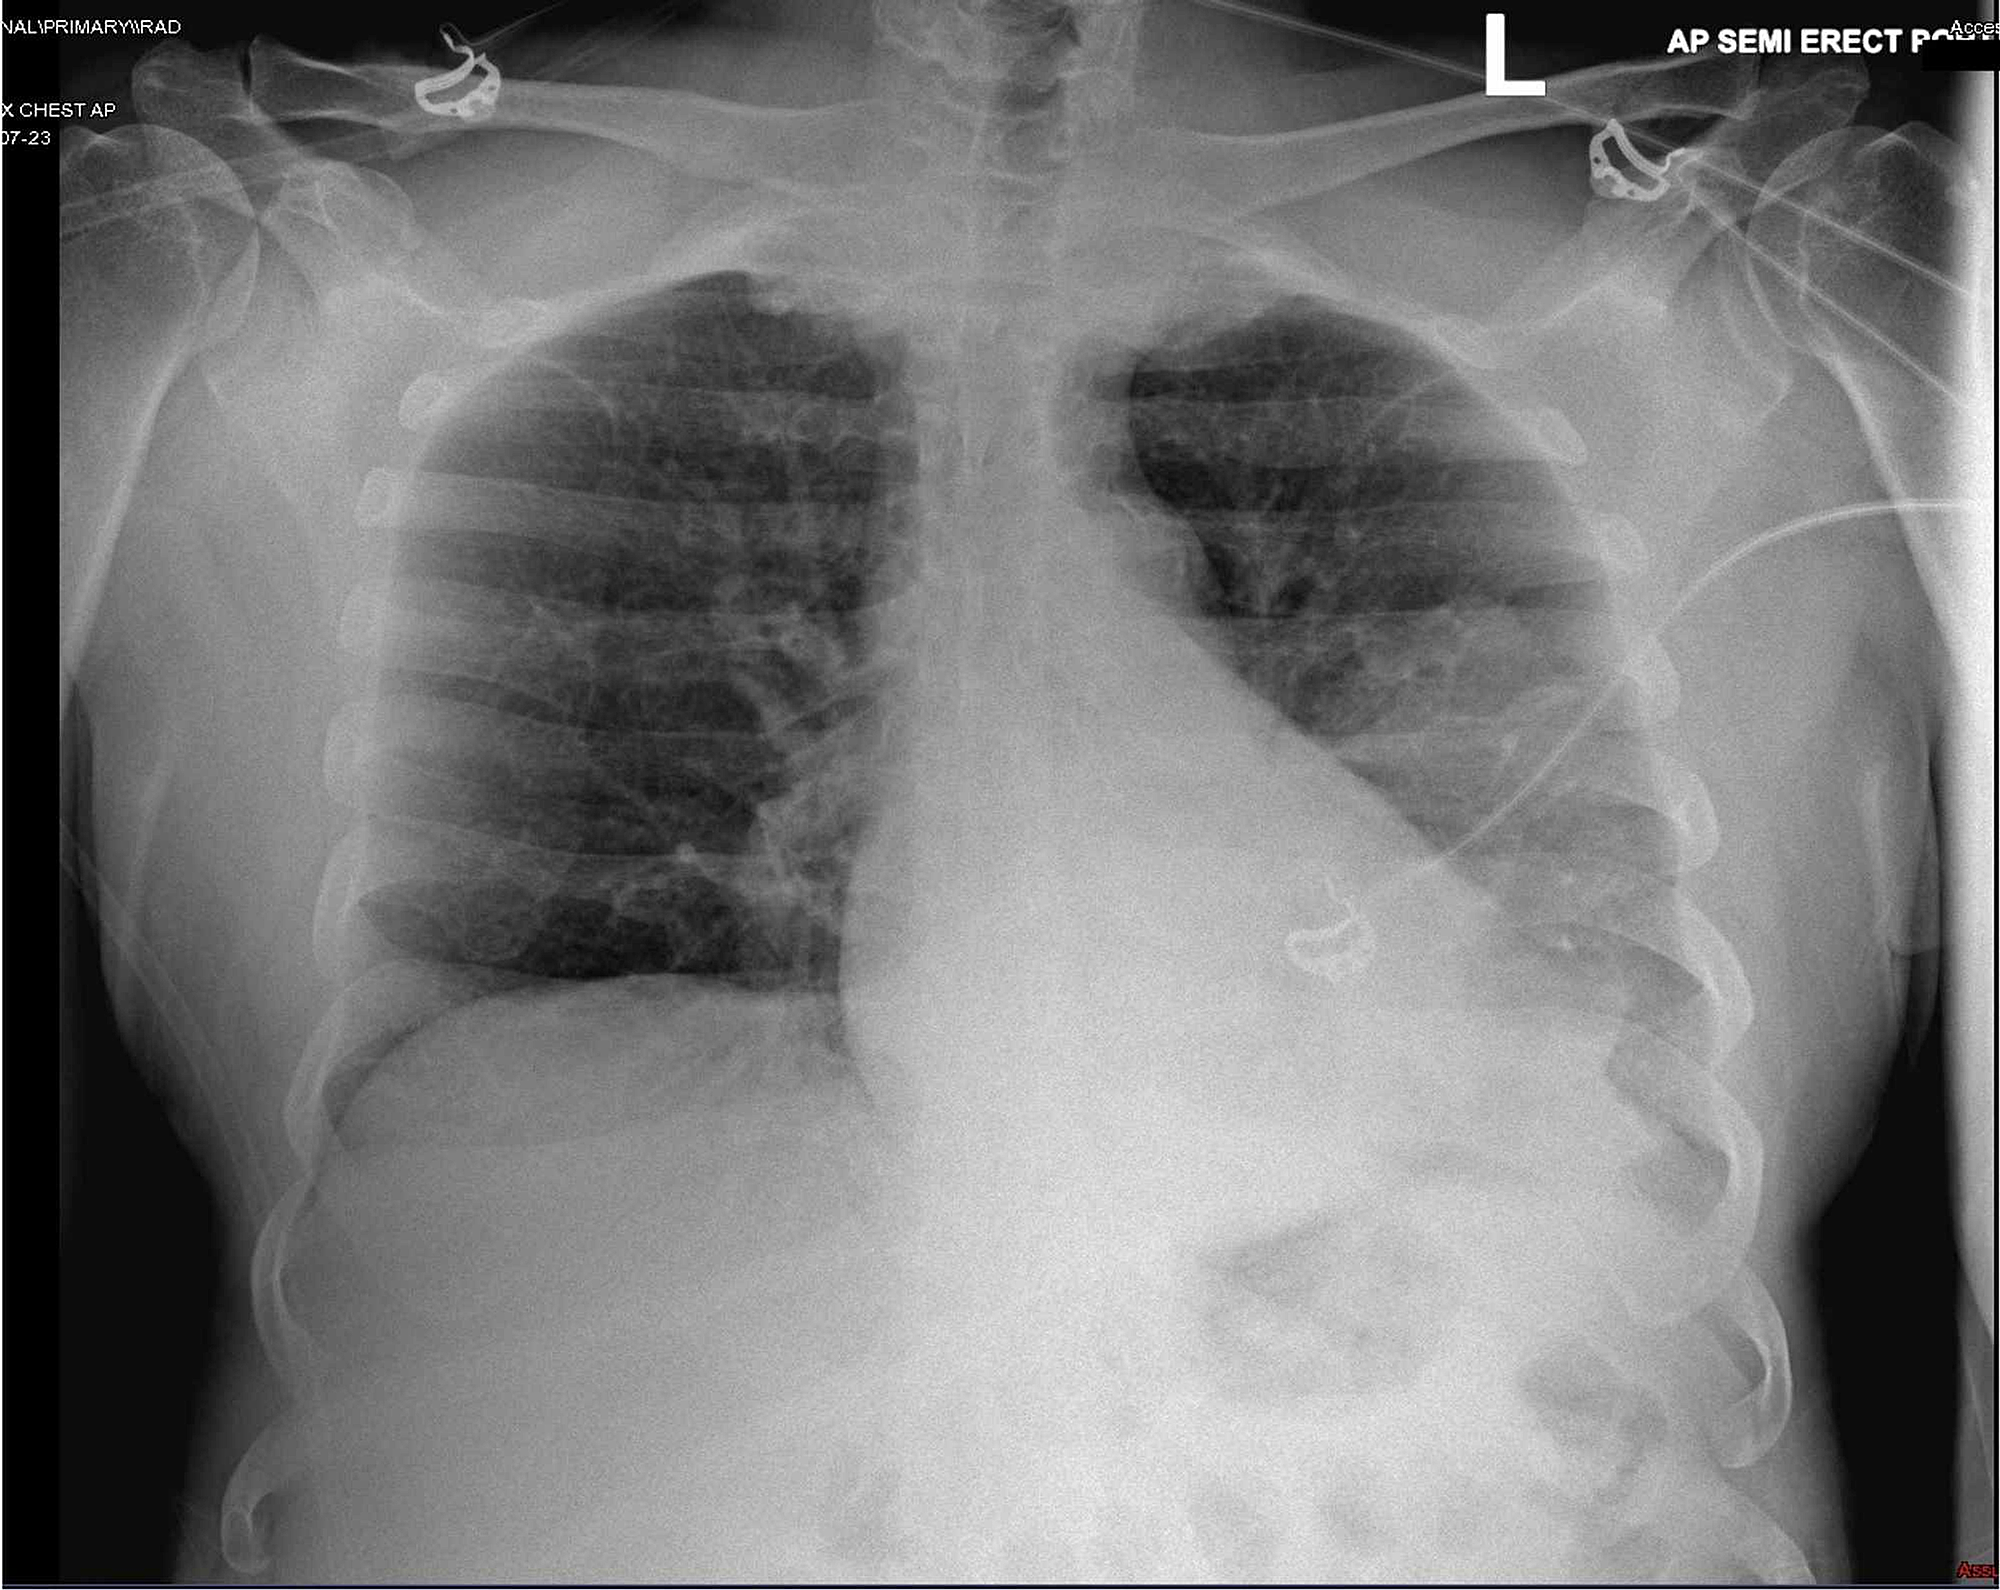

Septic DoubleSided Pneumonia. 100 Confirmed Diagnosis Stock Photo What Is Double Pneumonia And Sepsis Double pneumonia causes range from bacteria to fungi to viruses. Sepsis is a progression of an infection that can quickly turn into septic shock or even lead to death. Those that more commonly cause. When you have an infection, your immune system works to try to fight it. Sepsis is your body’s extreme reaction to an infection. Here's what you. What Is Double Pneumonia And Sepsis.